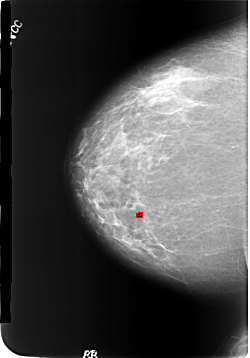

B_3186_1.RIGHT_CC

FILE: B_3186_1.RIGHT_CC.OVERLAY

TOTAL_ABNORMALITIES 1

ABNORMALITY 1

LESION_TYPE CALCIFICATION TYPE LUCENT_CENTER DISTRIBUTION N/A

ASSESSMENT 2

SUBTLETY 4

PATHOLOGY BENIGN_WITHOUT_CALLBACK

TOTAL_OUTLINES 1

BOUNDARY